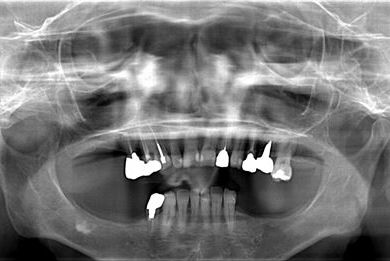

インプラントの症例写真 IMPLANT

骨再生インプラント治療+セラミック治療

| 治療内容 | インプラント6本(ソケットリフト)、ハイブリッドセラミック14本(ハイブリッドセラミック用土台5本、遊離歯肉移植術 | ||||||||||||||||||||||||||||||||

| 総治療費 | 2,751,445円 | ||||||||||||||||||||||||||||||||

| 治療期間 | 2年3ヶ月 |